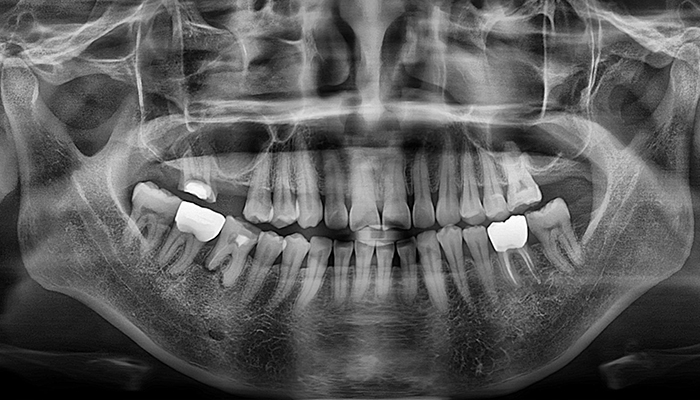

임플란트 수술시, 상악동과 잇몸뼈 사이에 뼈가 남아 있지 않았을 때 상악동막을 들어올리고 빈 공간에 뼈를 이식하여 임플란트 식립을 위한 공간을 확보하는 수술을 상악동 거상술이라 합니다.

밀도가 높고 두꺼운 턱뼈가 구성된 아래턱과는 달리 위턱은 얇은 뼈 위에 코와 광대 사이 빈 공간에 식립해야 하는 고난도 수술로 임플란트 수술 경험이 많은 의료진에게 받는 것이 중요합니다.

치아를 빼고 오래 방치하거나 치아를 잡고 있는 치조골이 많이 녹은상태에서 치아를 빼면 위쪽 턱뼈가 부족할 수 있습니다.